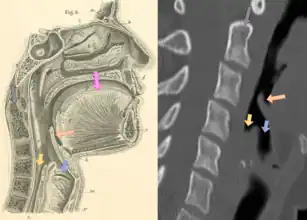

| Neck X-ray showing thumbprint sign. | |

Epiglottitis was historically mostly caused by infection by H. influenzae type b (commonly referred to as "Hib").[1] With vaccination, it is now more often caused by other bacteria, most commonly Streptococcus pneumoniae, Streptococcus pyogenes, or Staphylococcus aureus.[1] Predisposing factors include burns and trauma to the area.[1] The most accurate way to make the diagnosis is to look directly at the epiglottis.[3] X-rays of the neck from the side may show a "thumbprint sign" but the lack of this sign does not mean the condition is absent.[1]

On lateral C-spine X-ray, the thumbprint sign describes a swollen, enlarged epiglottis.[10] A normal X-ray, however, does not exclude the diagnosis.[10] An ultrasound may be helpful if specific changes are present, but its use (as of 2018) is in the early stages of study.[10]